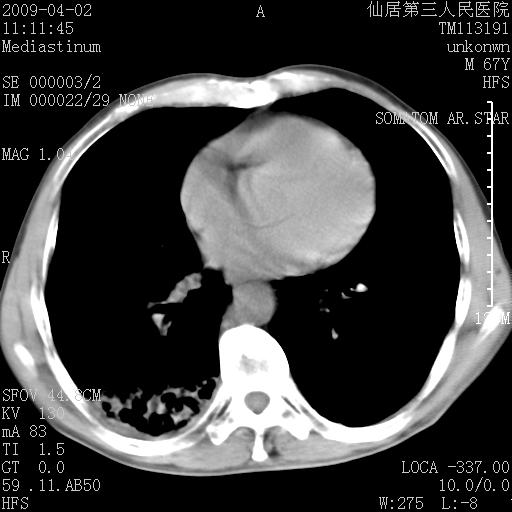

患者老年男性,乏力畏寒来诊,摄胸片示右下肺感染性病变,抗炎两周后复查胸片,无好转有进展。

后做ct平扫表现如下:

考虑右肺炎症可能性大,不除外细支气管肺泡癌

是否还要考虑肺间质纤维化,建议hrct扫描。

考虑间质性肺炎。

病灶呈蜂窝征,纵隔多个淋巴结肿大;肺泡癌需考虑

右肺下叶背段干酪性肺炎。请痰检[emb28]

我认为普通的感染应该可以除外,间质性肺炎可能性较大,但如何解释纵膈的淋巴结肿大呢

考虑双肺间质性改变(间质纤维化?)伴右肺下叶感染。